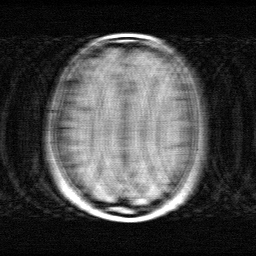

Ground Truth

Measurement (perturbed)

Reconstruction

Mean PSNR Across All Scenes

Per-scene PSNR breakdown (4 scenes)

| Scene | I (PSNR) | I (SSIM) | II (PSNR) | II (SSIM) | III (PSNR) | III (SSIM) |

| scene_00 | 16.369188751529634 | 0.3769596313670564 | 28.91599361455386 | 0.8937325593738555 | 43.0888232643681 | 0.9970601105022431 |

| scene_01 | 17.02984109629589 | 0.5076141905187631 | 29.54697836453365 | 0.9088858192167282 | 44.00498178524224 | 0.9974331602373123 |

| scene_02 | 19.876634796830935 | 0.5132084125883123 | 29.296469693787934 | 0.8901788054246903 | 45.80916505985154 | 0.9983439806976319 |

| scene_03 | 16.209230008064964 | 0.3451008090497886 | 28.211197909256423 | 0.8836538261470794 | 42.81516446798818 | 0.997371546825409 |

| Mean | 17.371223663180356 | 0.4357207608809801 | 28.99265989553297 | 0.8941127525405883 | 43.929533644362515 | 0.9975521995656491 |